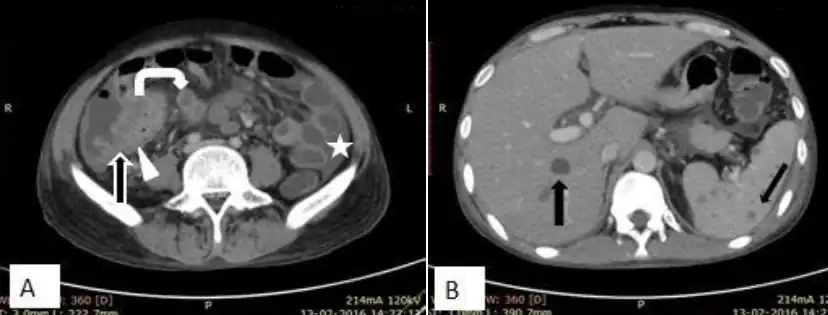

a,b)CT of abdominal tuberculosis[15] -

The clinical presentation of abdominal tuberculosis is often atypical, tissue samples for confirmation of diagnosis can be difficult to procure and conventional diagnostic methods have poor yield.[5] Therefore, the diagnosis is often delayed.[5] The diagnosis is often suspected clinically with relevant manifestations or epidemiological factors such as known prior tuberculosis and possible TB exposure.[13] A high index of suspicion of TB should be maintained in immunocompromised individuals.[13] Those with extra-abdominal tuberculosis should undergo evaluation for abdominal involvement in case of clinical suspicion. The definitive diagnosis can be established by demonstrating Mycobacterium tuberculosis in peritoneal fluid or in a biopsy specimen. The histopathologic findings of tuberculosis in biopsy, such as caseous granuloma, can be suggestive of tuberculosis, but is not pathognomic.[13] CT scan offers evaluation of involvement of the liver or other organs, as well as for the presence of ascites, lymphadenopathy and peritoneal involvement.[13] Ultrasound scan is useful for demonstrating lymphadenopathy and ascites.[14]